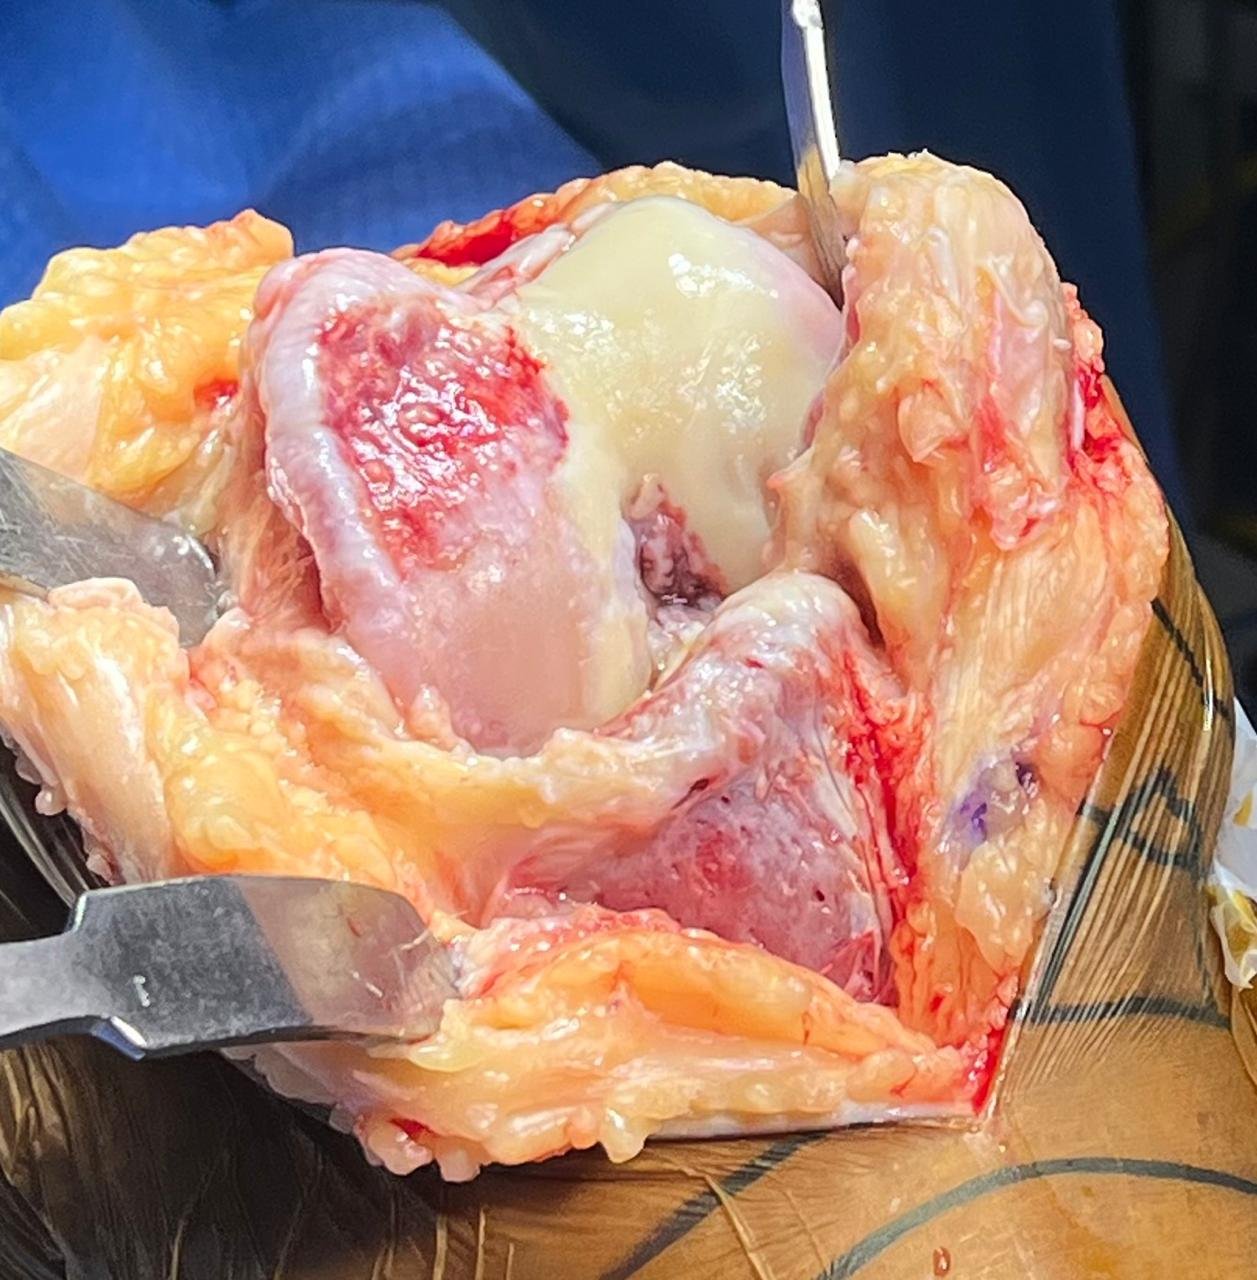

3. Surgery

Usual duration of surgery is 90-100 mins. The surgery principally aims at precise measured

resection of eroded cartilage & bone of knee joint, correction of deformity, appropriate

balancing of soft tissue.